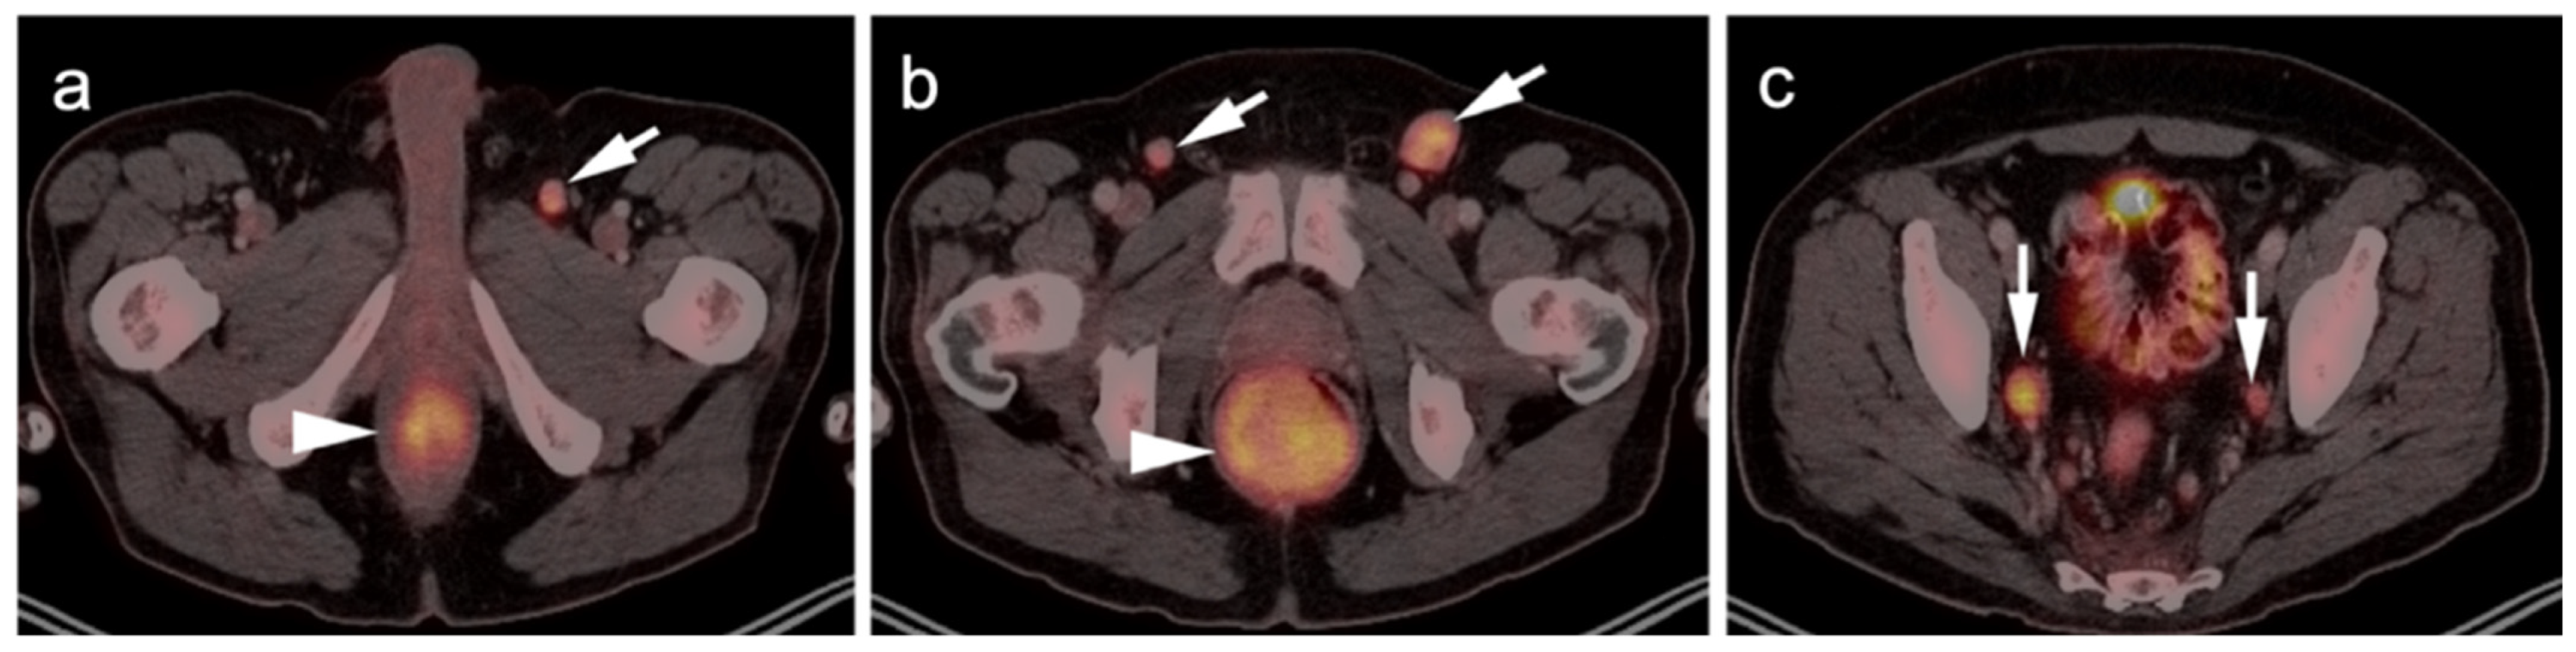

2.3.3. Mucosal Melanoma

- Falch, C.; Stojadinovic, A.; Hann-Von-Weyhern, C.; Protic, M.; Nissan, A.; Faries, M.B.; Daumer, M.; Bilchik, A.J.; Itzhak, A.; Brücher, B.L. Anorectal Malignant Melanoma: Extensive 45-Year Review and Proposal for a Novel Staging Classification. J. Am. Coll. Surg. 2013, 217, 324–335. [Google Scholar] [CrossRef]

- Murphy, G.; Hussey, D.; Metser, U. Non-cutaneous melanoma: Is there a role for18F-FDG PET-CT? Br. J. Radiol. 2014, 87, 20140324. [Google Scholar] [CrossRef] [Green Version]

- Falch, C.; Mueller, S.; Kirschniak, A.; Braun, M.; Koenigsrainer, A.; Klumpp, B. Anorectal malignant melanoma: Curative abdominoperineal resection: Patient selection with 18F-FDG-PET/CT. World J. Surg. Oncol. 2016, 14, 185. [Google Scholar] [CrossRef] [Green Version]